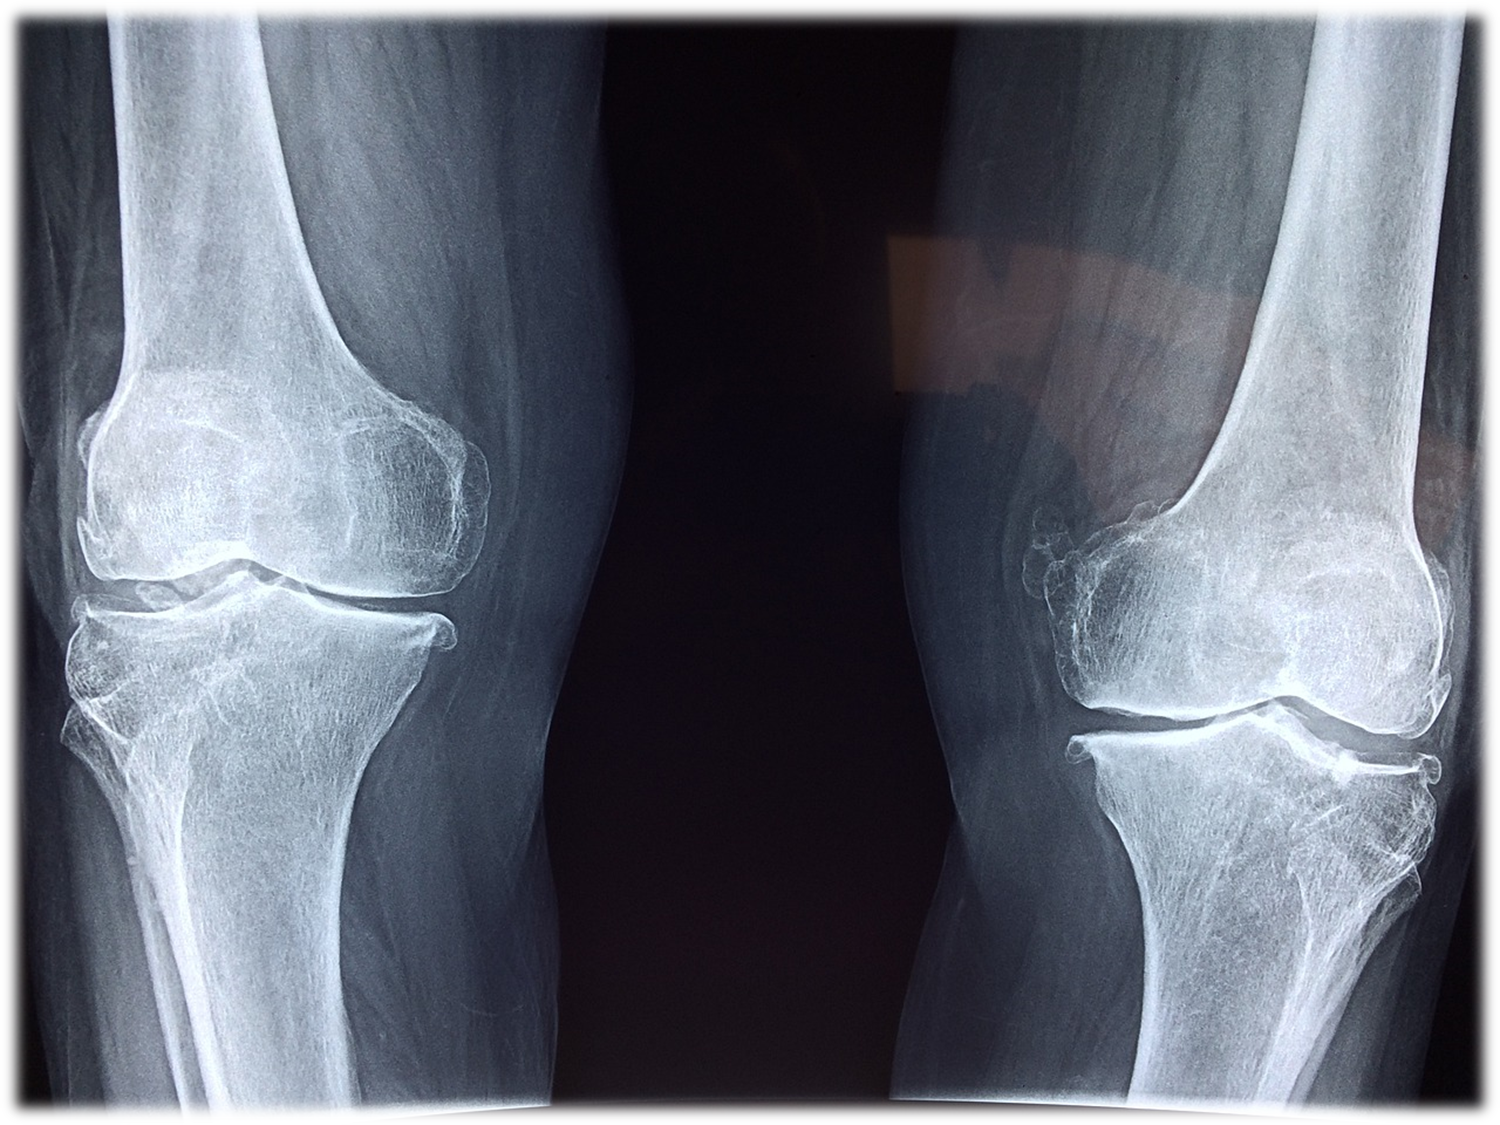

병원급의 의료기관 중 관절질환과 진료과목에 대해 특별히 높은 난이도의 의료행위를 하는 병원으로 해당질환과 진료과목에 대해 전문적인 진료 및 의료서비스를 제공하는 의료기관을 대상으로 보건복지부가 위탁한 심사평가원에서 전문심사를 거쳐 보건복지부가 3년마다 지정하는 제도를 이야기합니다.

그 중에서도 관절전문병원의 경우는 정형외과, 관절분에 에 특화된 병원으로 평가를 받고 지정받았다고 볼 수 있겠습니다.